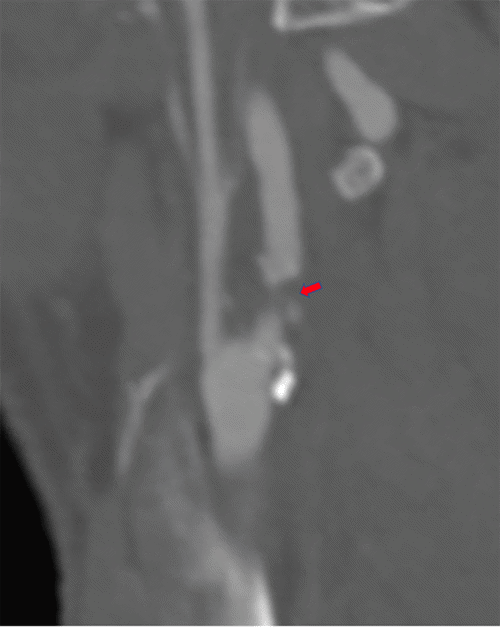

Bilateral carotid artery duplex demonstrated right internal carotid artery (ICA) peak systolic velocities (PSV) of 475 cm/s and end-diastolic velocities (EDV) of 180 cm/s, and left ICA PSV of 576 cm/s and EDV of 241 cm/s, consistent with >80% stenosis bilaterally. Vertebral artery flow was antegrade bilaterally. Dual antiplatelet therapy with aspirin 81 mg daily and clopidogrel 75 mg daily was initiated for stroke prevention upon review of this initial workup. CT angiogram corroborated severe stenosis of bilateral ICAs associated with ulcerated calcified plaque (Figure 1) and a focal dissection of the left distal ICA at the cervical level of mid-C2. Bilateral carotid bifurcations were at the level of the intervertebral space between C3 and C4 without heavy calcifications. Common carotid arteries were without disease, and the circle of Willis was intact.

Figure 1. Sagittal View of Preoperative Cervical CT Angiogram Demonstrating Severe Left A) and Right B) ICA Stenosis. Published with Permission

A.

B.